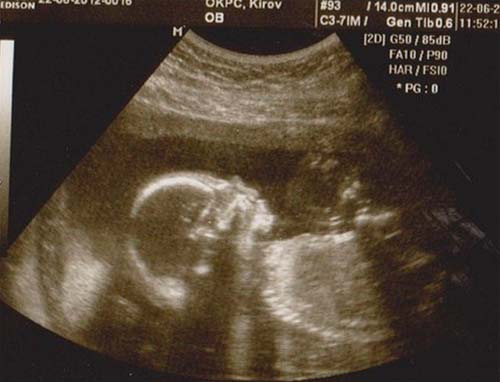

Se você não fez um ultrassom no segundo trimestre, ele será indicado. Um médico especialista verificará as principais dimensões do corpo e membros do feto, a condição dos órgãos internos e vários outros indicadores. A placenta não será menos minuciosamente examinada.

Foto de ultrassom com 21 semanas (clique para ampliar):

Com uma localização bem-sucedida do feto, você pode descobrir o sexo do bebê. Mas o futuro menino ou menina às vezes pode "esconder" até o nascimento.